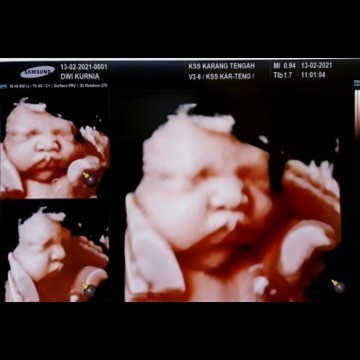

Alhamdulillah si adek sudah launching usia 39week👶 Alhamdulillah normal bb 3,2kg walaupun ada drama saat melahirkan tp bahagia pas liat malaikat kecil lahir🤗untuk bunda" cantik yg menunggu gelombang cinta semangat ya..semoga lancar persalinannya, ibu dan debaynya sehat🙏🏻 #Second_Baby #babyboy #39week #alhamdulilahsehatibudanbaby #MasyaAllahTabarakaAllah